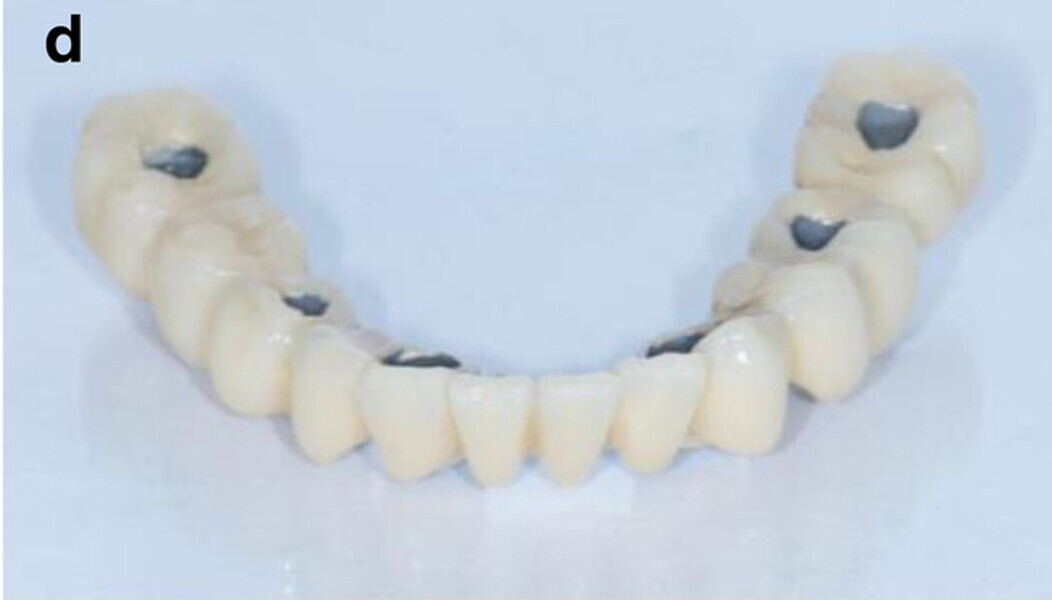

Fig. 13a: CAD/CAM-fabricated one-piece cobalt–chromium framework before (a & b) and after veneering with composite (SR Nexco Paste, Ivoclar Vivadent), that is the final FDP (c & d).

Fig. 13b: CAD/CAM-fabricated one-piece cobalt–chromium framework before (a & b) and after veneering with composite (SR Nexco Paste, Ivoclar Vivadent), that is the final FDP (c & d).

Fig. 13c: CAD/CAM-fabricated one-piece cobalt–chromium framework before (a & b) and after veneering with composite (SR Nexco Paste, Ivoclar Vivadent), that is the final FDP (c & d).

Fig. 13d: CAD/CAM-fabricated one-piece cobalt–chromium framework before (a & b) and after veneering with composite (SR Nexco Paste, Ivoclar Vivadent), that is the final FDP (c & d).